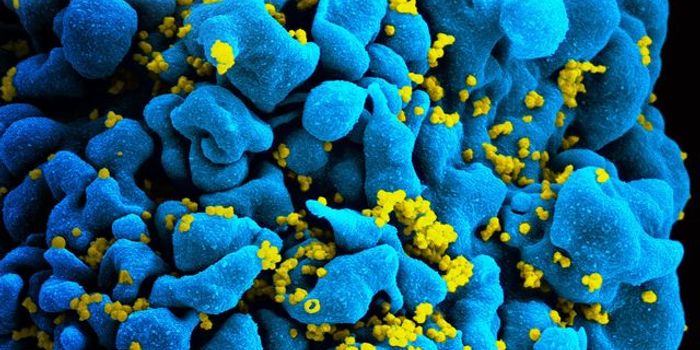

DEC 04, 2018ImmunologyA team of scientists discover unique immune reactions to the one percent of HIV infected patients that are able to fend ...